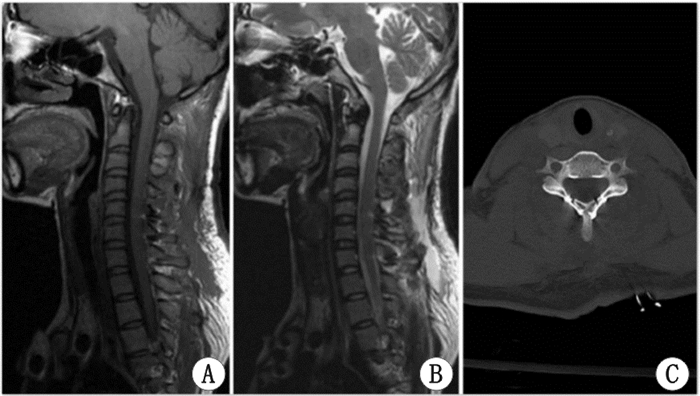

| 在完全性脊髓损伤15 h后,急诊行椎板切开血肿减压术,术后行椎板重建。图A和图B分别为术后复查MRI的矢状位T1加权和T2加权。图C为术后横断位CT。术后神经功能即有恢复。术后6个月随访JOA评分17分 图 2 术后MRI和CT Fig 2 MRI and CT after surgery |

3.3 影像与诊断急性起病的患者病情进展迅速,早期诊断主要依靠CT及MRI。脊椎CT主要表现为椎管内占位性病变,占位呈高密度影,矢状位呈梭形、边界清楚,硬膜囊明显受压变形。MR能更加清晰地显示椎管内占位的部位、范围及与脊髓、硬脊膜的关系。急性期的出血(<3 d)在T1WI为等或稍高或混杂的信号[11],在T2WI为高信号影的外周和低信号的血肿中心[12]。进入亚急性期后(出血后3~14 d),T1及T2加权在信号上均逐渐增高,在亚急性末期,因为含铁血黄素的沉积,外周开始出现低信号[11]。Groen和Van Alphen[13]统计文献报道330例SEDH发病部位以颈胸部及胸腰部最为常见,约占77%,且血肿多位于椎管后方,脊髓的背侧。这可能是因为硬脊膜腹侧与椎体贴近,相对活动少,不易形成血肿。